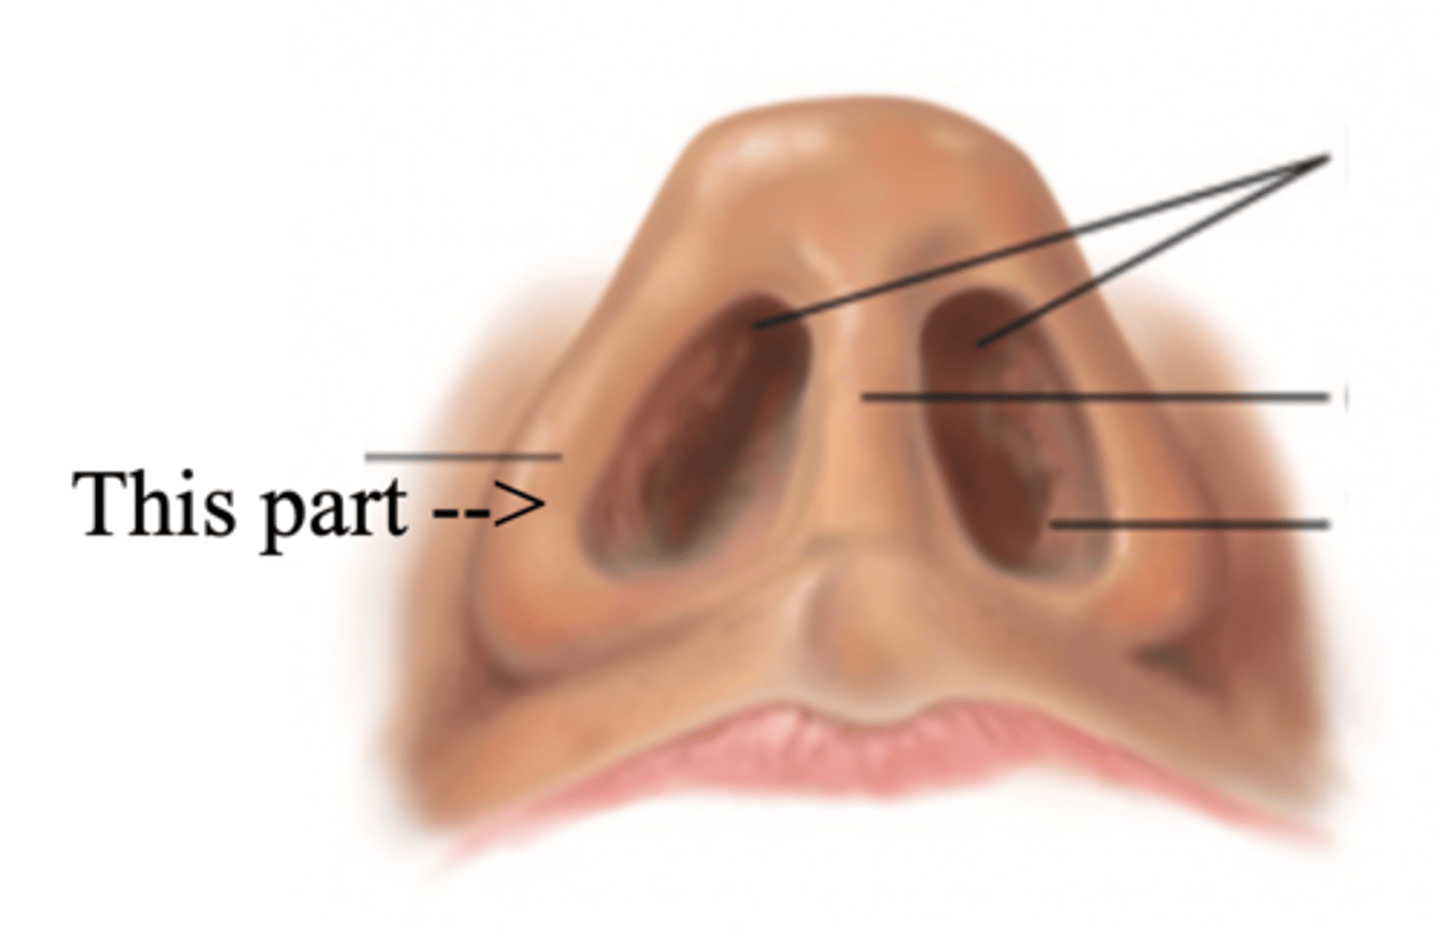

Ala